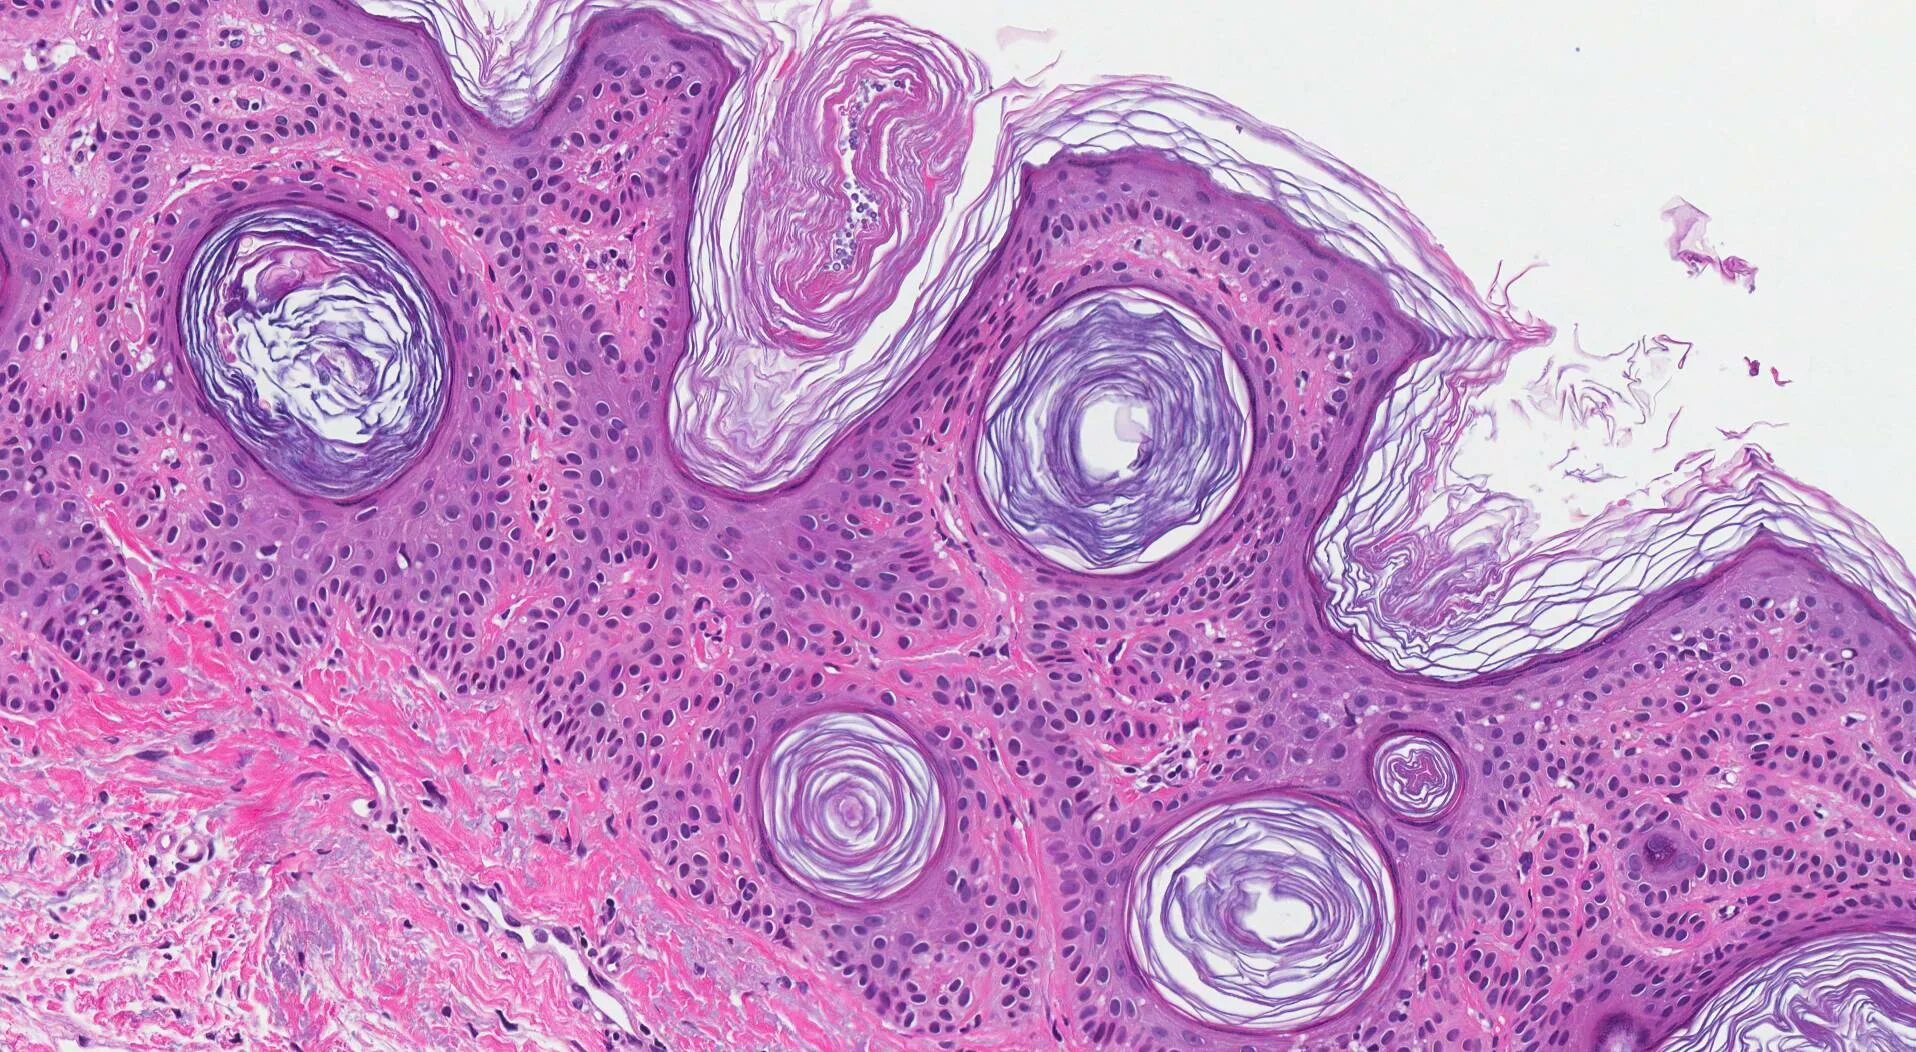

Гистологические варианты